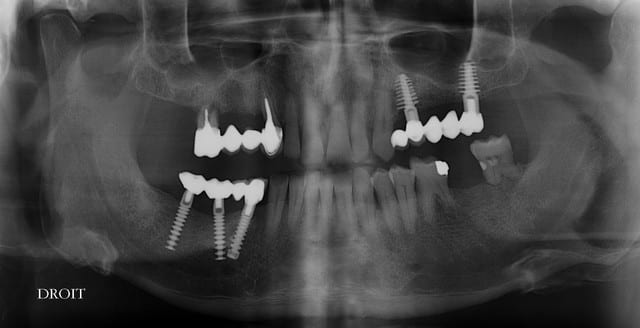

13 fenestration vestibulaire j'utilise la paroi palatine, lame N°15, spreader, expansion et pose d'un 40140

Puis 40120 en 15 avec léger SL, à l'ostéotome, et 40120 en 17.

Le pano est d'avant les extractions

oui, bien sur ce sont des Tatum D1 en bas et D4 en haut